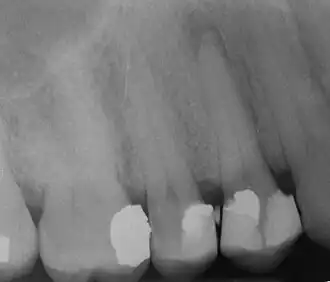

Radiograph showing bone loss between the two roots of a tooth (black region). The spongy bone has receded due to infection under tooth, reducing the bony support for the tooth.